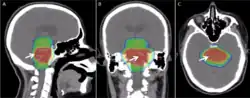

Modern radiation therapy relies on a CT scan to identify the tumor and surrounding normal structures and to perform dose calculations for the creation of a complex radiation treatment plan. The patient receives small skin marks to guide the placement of treatment fields.[10] Patient positioning is crucial at this stage as the patient will have to be placed in an identical position during each treatment. Many patient positioning devices have been developed for this purpose, including masks and cushions which can be molded to the patient. Image-guided radiation therapy is a method that uses imaging to correct for positional errors of each treatment session.

Delivery parameters of a prescribed dose are determined during treatment planning (part of dosimetry). Treatment planning is generally performed on dedicated computers using specialized treatment planning software. Depending on the radiation delivery method, several angles or sources may be used to sum to the total necessary dose. The planner will try to design a plan that delivers a uniform prescription dose to the tumor and minimizes dose to surrounding healthy tissues.

The planning of radiation therapy treatment has been revolutionized by the ability to delineate tumors and adjacent normal structures in three dimensions using specialized CT and/or MRI scanners and planning software.[81]

An enhancement of virtual simulation is 3-dimensional conformal radiation therapy (3DCRT), in which the profile of each radiation beam is shaped to fit the profile of the target from a beam's eye view (BEV) using a multileaf collimator (MLC) and a variable number of beams. When the treatment volume conforms to the shape of the tumor, the relative toxicity of radiation to the surrounding normal tissues is reduced, allowing a higher dose of radiation to be delivered to the tumor than conventional techniques would allow.[10]